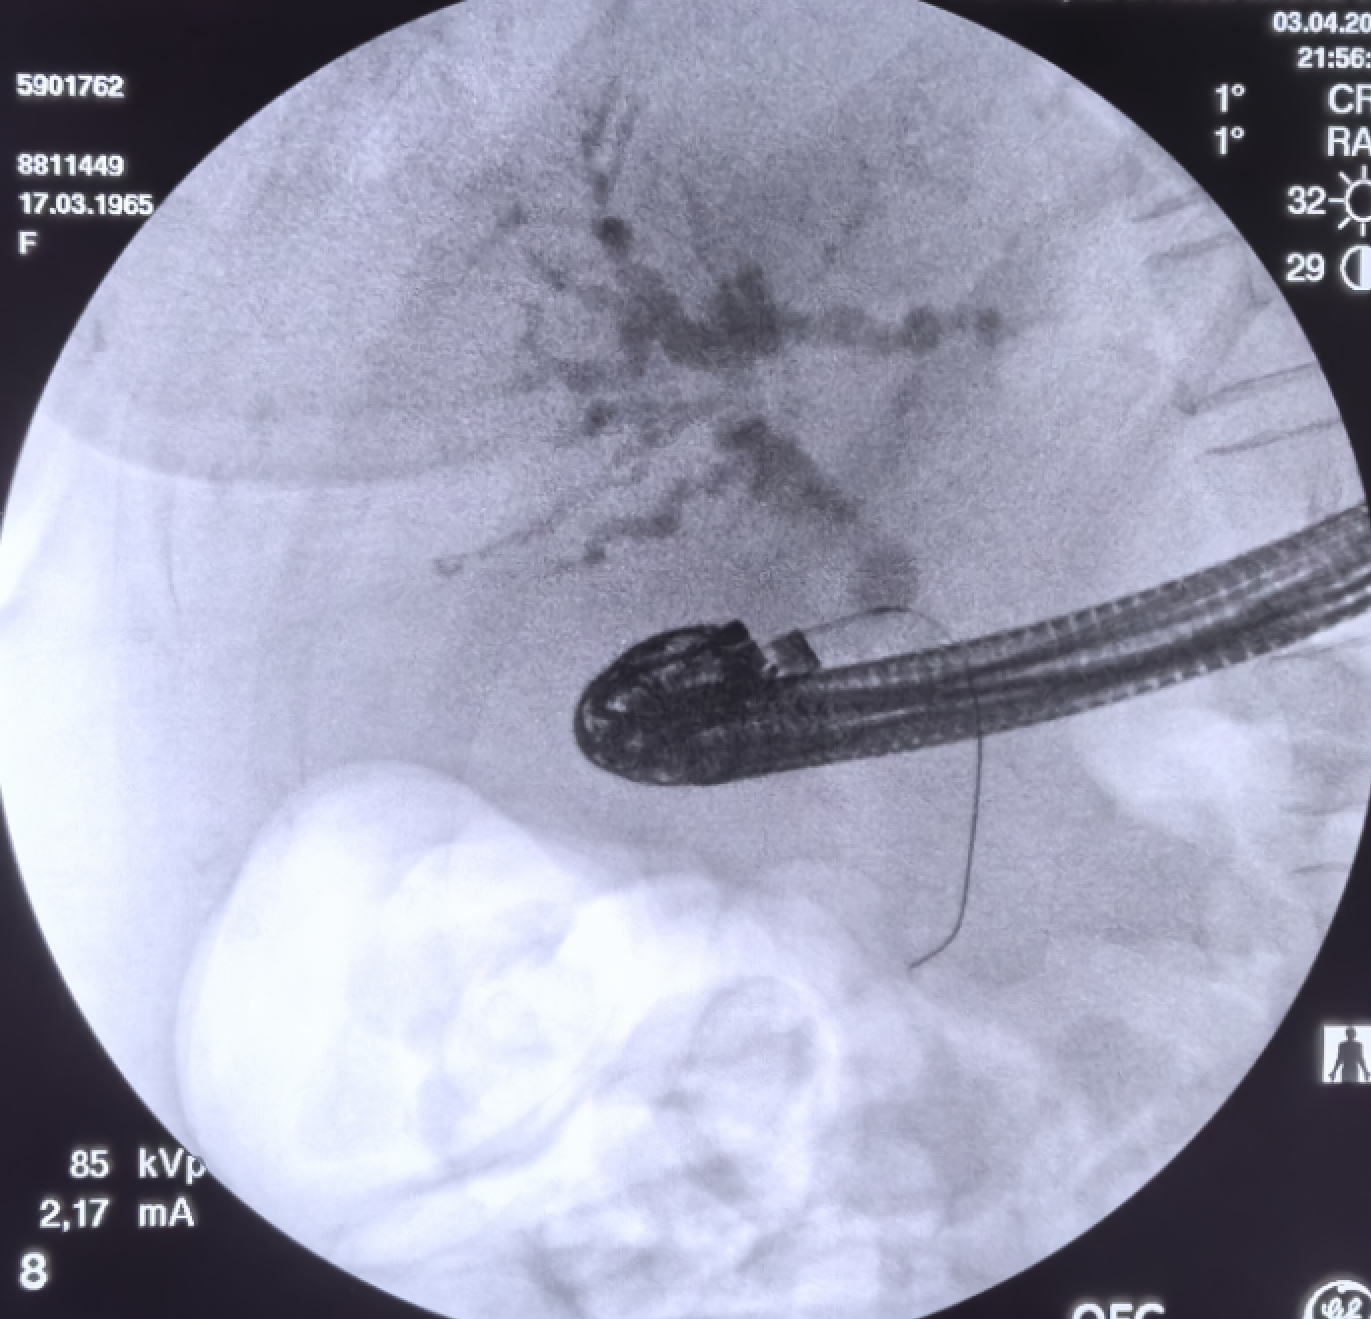

造影

微信图片_20240727120136.png

进入导丝,但发现导丝反复进入胆管下游,而此患者十二指肠降部狭窄,又不能行会师技术,胆总管下段狭窄段比较长,不宜行顺行